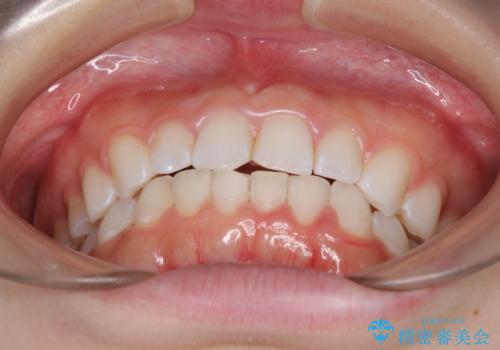

デコボコと深い咬み合わせの改善 インビザラインによる矯正治療

- 口元のデコボコと深い咬み合わせ(ディープバイト)を気にして来院された患者様です。

インビザラインによる上下歯列の拡大と、IPR(歯と歯の間を削る)にるスペースの獲得により、口元のデコボコとディープバイトを改善することとしました。

インビザラインは、装着していない時間がどれだけ短いかが、治療期間を大きく左右します。こちらの患者様は1日22時間以上、毎日欠かさず装着してくださったため、1年強という短期間で満足のいく歯列に整えることができました。